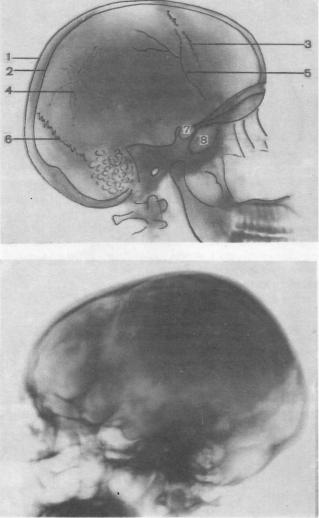

Анатомия детского черепа: Рентгеновские снимки и описание